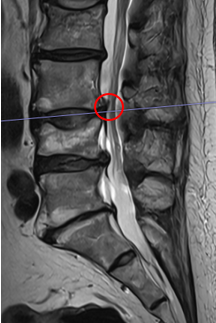

治療後

術後から2週間後には腰痛、右お尻から足にかけての痛み・痺れともに10点から2点に軽減したとのことです。術後のMRIでは椎間板ヘルニアが減少して小さくなっているのが確認できております。